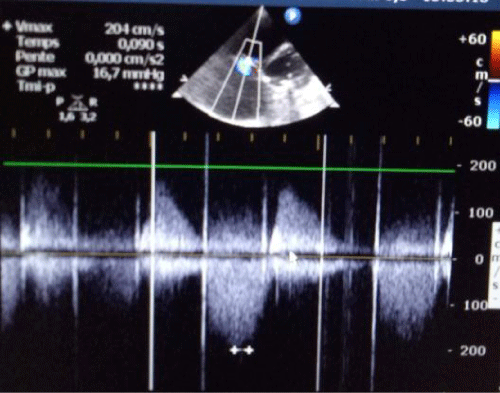

Six month later, the patient was readmitted to hospital because of dyspnea and peripheraledema, Transthoracic echo cardiography revealed moderate right ventriculardysfunction and recurrence of TS (Figure 4,5) with mild TR (Figure 4), we decided to perform PTTBV but we had to stop the preocedure due to uncrease of tricuspid regurgitation.